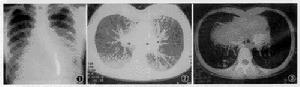

肺大疱